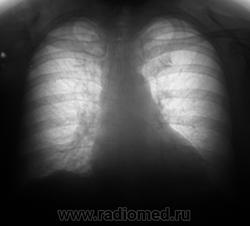

Флюорограмма - 2009 год.